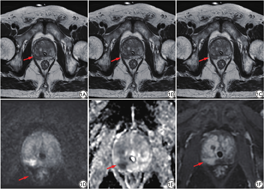

所有患者横断位常规T2WI、快速T2WI序列和DLR快速T2WI图像清晰,图像质量均能满足诊断要求(图1)。两名诊断医师对于整体图像质量、伪影、前列腺包膜显示清晰度、前列腺病变显示清晰的主观评分的一致性较好(ICC=0.71~0.86,P均<0.05),其中前列腺包膜显示清晰度评分的一致性最高(ICC=0.86,P<0.05),详见表2。两位影像科医师的评分结果均显示,常规FSE-T2WI、快速FSE-T2WI和DLR快速FSE-T2WI的整体图像质量评分、前列腺包膜显示清晰度和前列腺病变显示清晰度均存在显著差异(P均<0.05);但在伪影评分上差异无统计学意义(表3)。

在外周带、移行带和病灶的SNR方面,DLR快速FSE-T2WI均明显高于常规FSE-T2WI和快速FSE-T2WI(P<0.05);DLR快速FSE-T2WI上,前列腺外周带、移行带和病灶的SNR分别为(476.9±444.4)、(331.4±274.3)和(324.1±390.1);在外周带、移行带和病灶与髂腰肌的CNR方面,DLR快速FSE-T2WI也均明显高于常规FSE-T2WI和快速FSE-T2WI(P<0.05)(表5)。

在此项前瞻研究中,我们比较了常规FSE-T2WI、快速FSE-T2WI和DLR快速FSE-T2WI对于前列腺MRI图像质量和扫描时间的影响。研究结果表明,DLR可以明显缩短T2WI扫描时间,比常规FSE-T2WI的扫描时间减少超过三分之一。在图像质量方面,DLR快速FSE-T2WI的前列腺外周带、移行带的SNR和CNR均显著高于无DLR的快速FSE-T2WI和常规FSE-T2WI。主观评分方面,DLR快速FSE-T2WI的整体图像质量最高,对于前列腺包膜的解剖结构和前列腺病灶的显示清晰度最高。